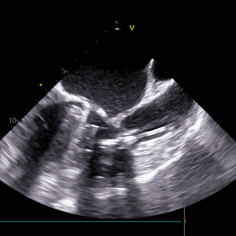

3. 全程无造影剂超声引导下行TAVI手术对超声团队高精度和快速判断要求极高,了解手术过程并同频配合术者手术操作,同时要求术者对超声解读深刻。

术中导丝跨瓣后20mm球囊预扩,超声判断冠脉风险尚可,植入L23 VenusA Plus可回收瓣膜位置良好,用23mm球囊后扩支架下缘,微少量瓣周漏。

术后即刻血压135/65mmHg,狭窄解除,释放后超声测量瓣下支架长度6mm标准位释放瓣膜位置完美。整台手术用时不足1.5小时,麻醉、超声等团队全程协作为手术顺利完成保驾护航。